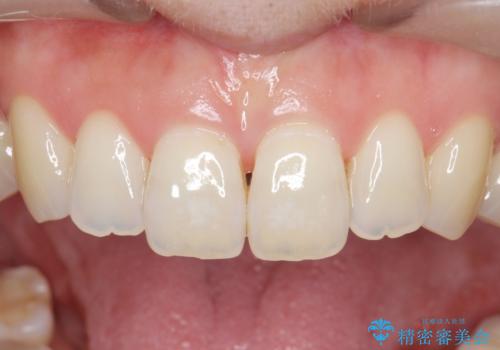

- 食いしばりがひどくてセラミックの被せ物が欠けたとの事で来院。

欠けたセラミックを新しいセラミックに変えた後、今後欠けたり割れたりしないように

ナイトガード(自費)を作製しました。